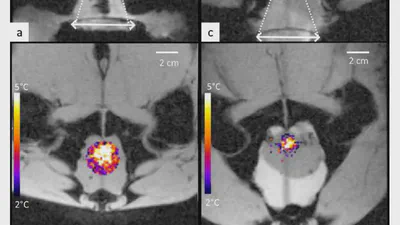

A novel concept of transperineal focused ultrasound transducer for prostate cancer local deep hyperthermia treatments

transperineal ultrasound hyperthermia for prostate treatment